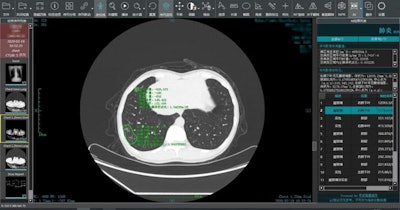

Ping An's algorithm can analyze medical images for signs of infection with COVID-19. Image courtesy of Ping An Insurance.Ping An's algorithm can analyze medical images for signs of infection with COVID-19. Image courtesy of Ping An Insurance.

Clinical data were used to train AI model to detect signs of COVID-19 infection in patients. It can conduct a comparative analysis of multiple CT scans of the same patient and measure changes in lesions. It assists doctors in diagnosing, determining the severity of the patients' conditions, and evaluating patients for COVID-19 swiftly and effectively, according to the company.